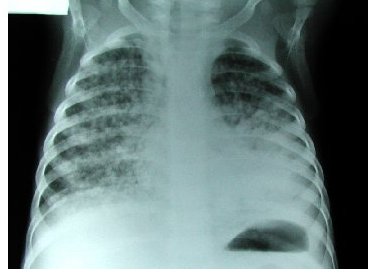

Diego es un niño alamos

Patrón radiológico: Diseminación difusa y puntilleo en todos los pulmones “alpiste de los canarios”, “semillitas cafés”.¿Que tratamiento le vas a dar?

A

Dotbal (RIPE)

rifampicina, isoniazida piranzinamida & etambutol o estreptocina

10 W x 4 tabletas 1 dosis

TB o Hongos! Mayor riesgo de meningitis tuberculosa.

A LA MADRE SE LE PASO LA BCG